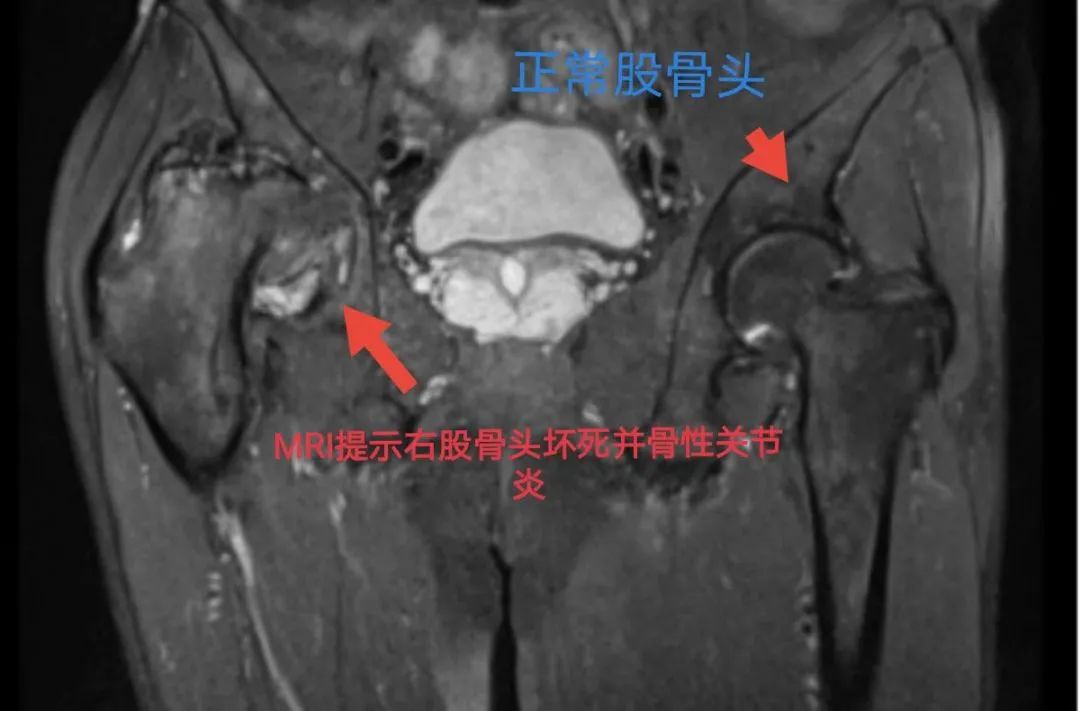

受尽病痛折磨的伍叔叔四处求医治疗,经朋友介绍,伍叔叔来到我院骨科。骨科副主任傅升培副主任医师对其进行了详细的检查。会诊后,综合考虑患者出现典型股骨头坏死三大症状:疼痛、功能受限、跛行,并结合DR、CT、MRI所见所见,明确诊断:股骨头坏死Ⅳ期。对于股骨头坏死Ⅳ期的治疗方案,目前已非常明确,就是行人工全髋关节置换术。